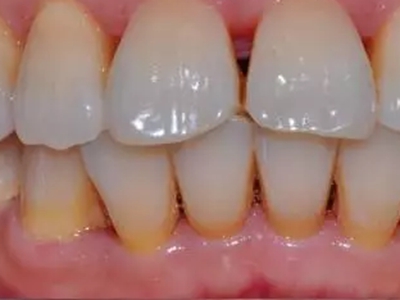

牙龈退缩露出淡黄色牙根图

牙龈退缩患者的牙龈退缩后,淡黄色牙龈明显露出。若进一步发展,易使对应位点的牙槽骨发生骨吸收,可能诱发龋齿、牙龈敏感、菌斑堆积等。